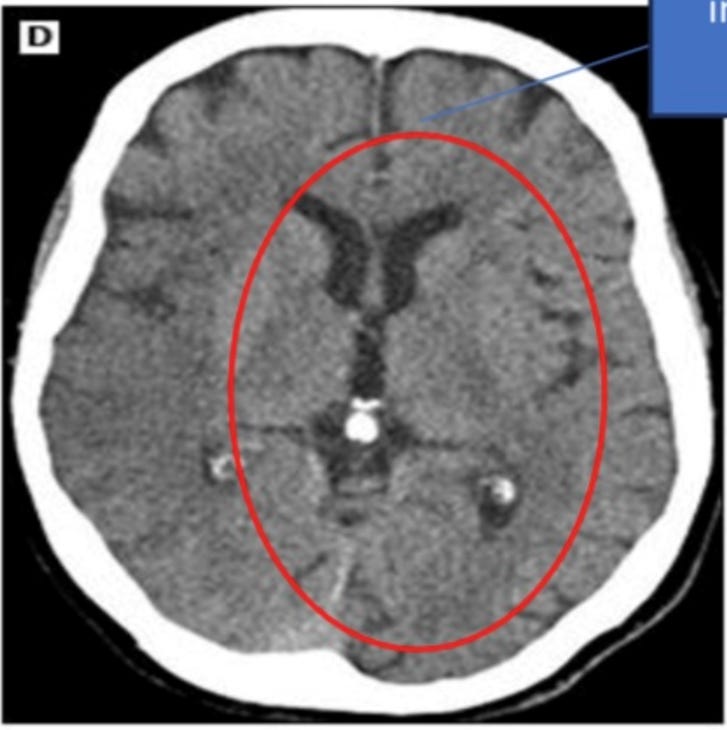

Mon patient a subi plusieurs examens d'imagerie révélant la présence de micropuces implantées. Ces emplacements correspondaient aux zones de torture les plus sévères. Ci-dessous, vous pouvez voir une micropuce entourée :

Voici une dans le cerveau :